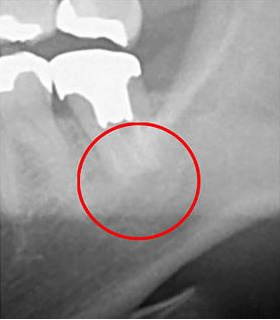

以下の画像は、同じ患部をCTとレントゲンで撮影したものです。

左の写真がCTで、右の画像がレントゲンによるものです。赤丸で示された部分には黒い影が見え、ここには炎症が発生しています。しかし、レントゲンの写真ではその影が確認できません。

つまり、レントゲンのみの診断ではこの炎症を見逃す可能性が高くなります。気付かない間に炎症が悪化し、場合によっては抜歯が必要になることも考えられます。当院では、こうした事態を防ぐために、CTによる詳細な診断を徹底しています。